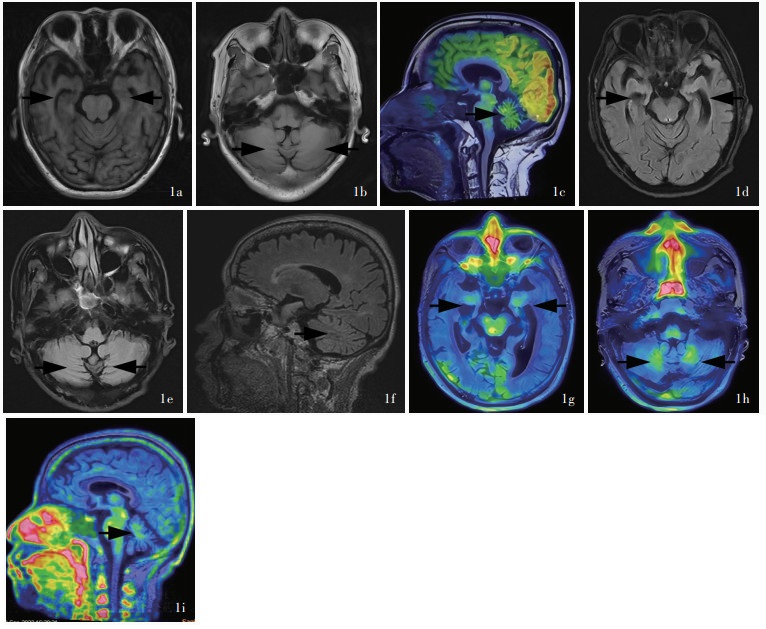

Shen R , Shen D , Zhou Q , Zhang M , Chen S . Antibody-mediated autoimmune encephalitis evaluated by 18F-DPA714 PET/MRI. Brain Behav Immun Health, 2022, 26: 100535.

Zhang Y , Zhou Q , Peng L , Chen S . Increased cerebellum 18F-DPA-714 uptake in anti-glutamate kainate receptor subunit 2 autoimmune encephalitis. Ann Neurol, 2023, 93: 635- 636.